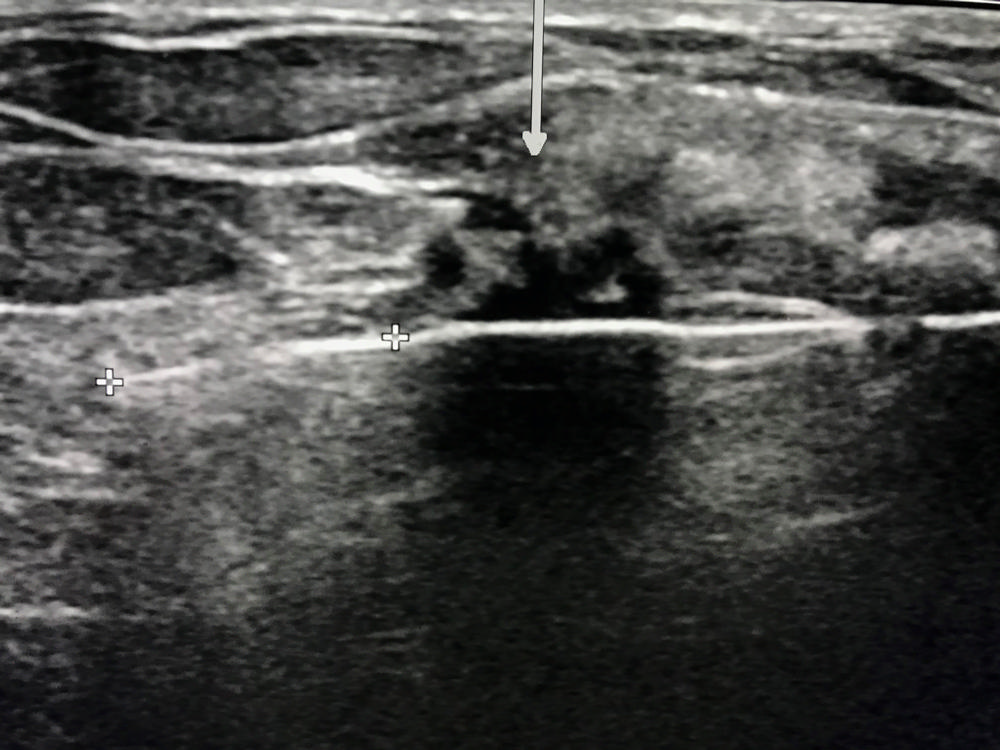

Figure 2. : Ultrasound of Figure 1 cancer prior to cryoablation (arrow). White line through cancer is cryoablation probe (+).

High-res (TIF) version